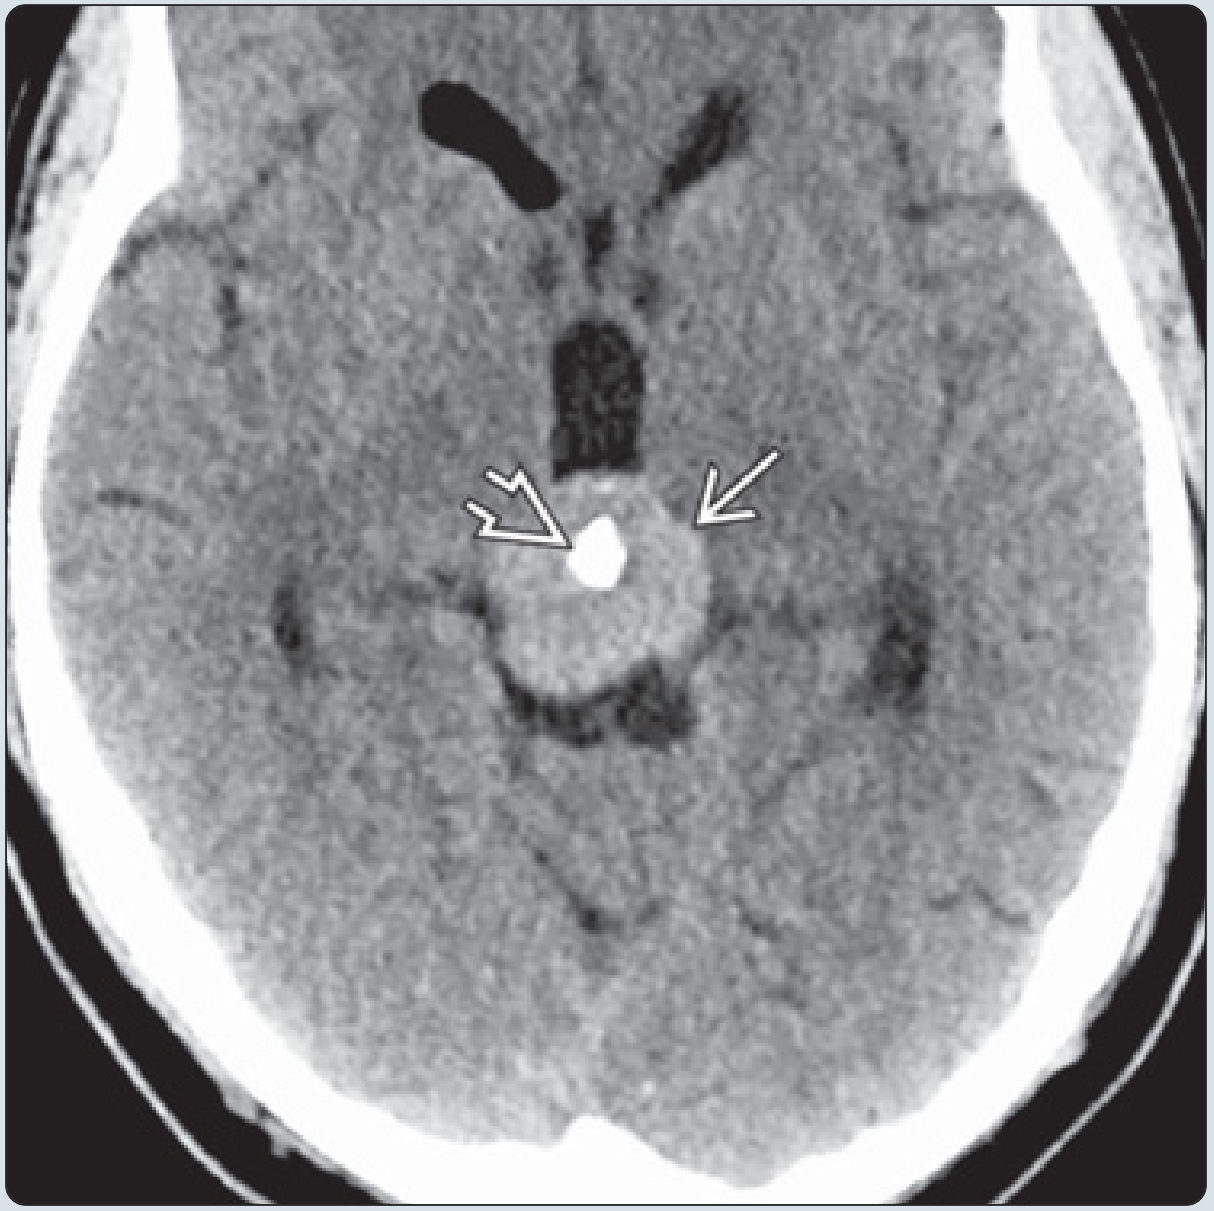

轴位CT扫描示典型的松果体生殖细胞瘤,可见边界清楚的稍高密度肿块包绕钙化的松果体。

生殖细胞瘤还有两个好发部位,一个是松果体区,其常常包绕松果体本身钙化,而另一个好发部位是基底节区,其几乎只见于男性,其常伴患侧邻近脑实质、脑干萎缩,可见华勒氏变性。